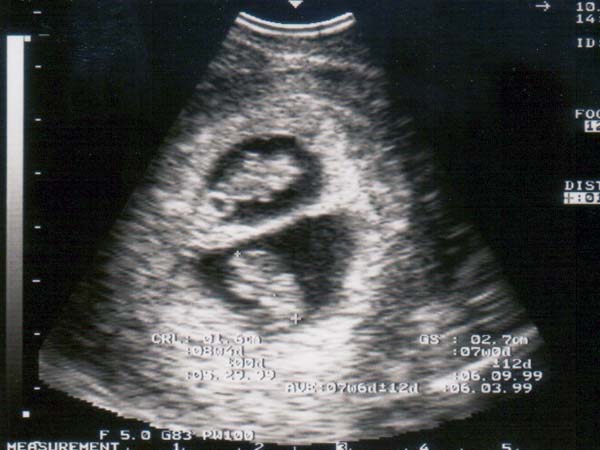

अगर प्लान कर रहे हैं जुड़वा बच्चे तो अपनाएं ये सरल उपाए

जुड़वा बच्चों को लेकर और भी कई कौतुहल लोगों के मन में बना रहता है। शादी के लंबे समय के बाद कपल जब बच्चें प्लान करते हैं तो ज्यादात्त्तर लोगों के मन में पहली चीज आती है कि काश जुड़वा बच्चें हो जाएं। माता-पिता बनना हर इंसान के लिए दुनिया की सबसे बड़ी चीज है। ऐसे में जब किसी महिला को जुड़वां बच्चे (twins) हो जाते हैं तो घर पर खुशी का माहौल दुगना हो जाता है। वहीं इसका एक फायदा भी हैं कि जुड़वा बच्चे करने की वजह से किसी भी महिला को बार-बार प्रसव पीड़ा (labour pain) से गुजरना नहीं पड़ेगा। ऐसे में अगर आप जुड़वा बच्चे चाहते हैं तो आज हम आपको इसका बेहद सरल उपाय बताएंगे।

सामान्य रूप से आईवीएफ के जरिए गर्भधारण करने वाली 20 से 40 प्रतिशत महिलाएं एक बार में एक से ज्यादा बच्चों को जन्म देती हैं। इसकी मुख्य वजह यह होती है कि इस दौरान महिला की योनि में एक से ज्यादा निषेचित अंडे डाले जाते हैं। ऐसे में आईवीएफ की मदद से आप जुड़वा बच्चे पा सकती हैं।